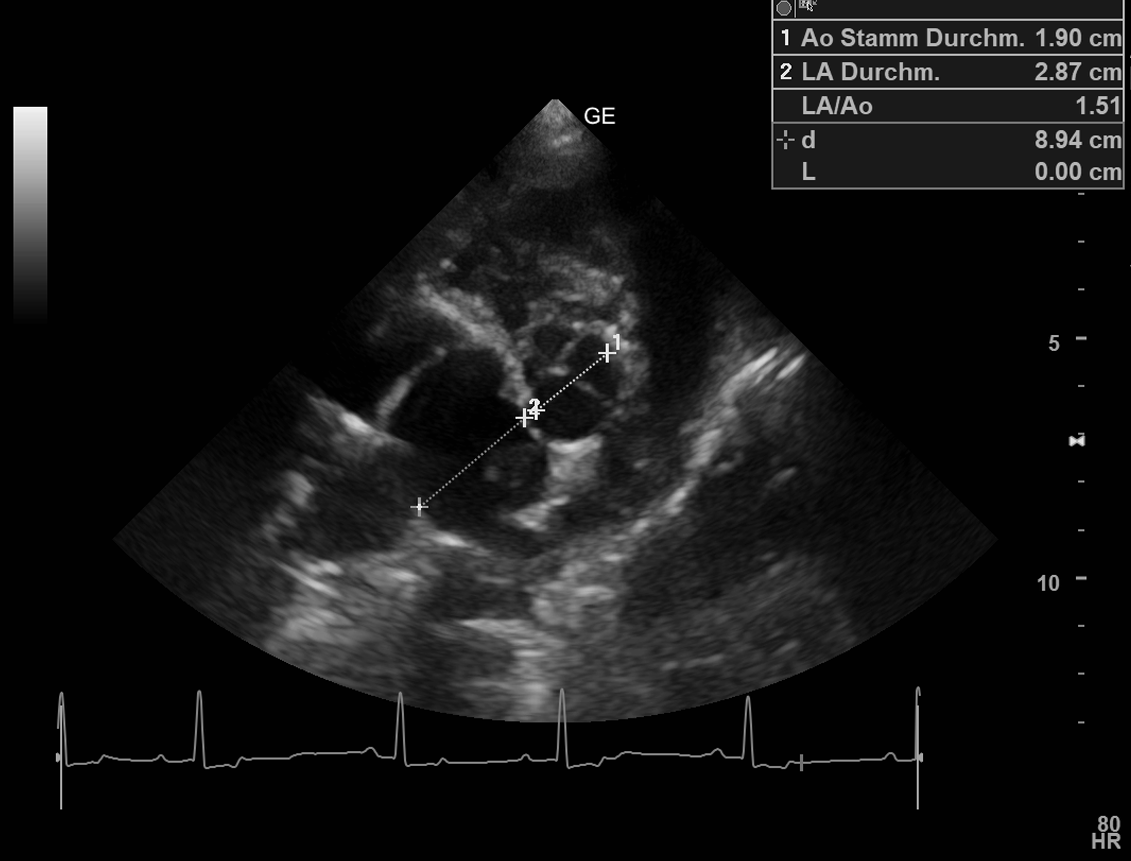

Leidet Ihr Tier an einer Herzerkrankung, kann diese mittels Auskultation (Abhören des Herzens) erkannt werden. Sind während der Auskultation des Herzens pathologische Geräusche des Herzens hörbar, empfiehlt sich eine Herzultraschalluntersuchung, die im Kleintierzentrum Landwasser routinemäßig durchgeführt wird. Dies ermöglicht eine genaue Diagnose des Herzleidens. Eine Sedierung des Tieres ist nicht notwendig und Sie können bei der Untersuchung selbstverständlich dabei sein. Wir haben mehrere Ultraschallköpfe zur Verfügung, um die kardiologische Untersuchung angepasst an die Größe Ihres Tiers durchzuführen. Mittels Farbdoppler können Blutströmungen in allen vier Herzkammern farblich dargestellt werden. Treten Undichtigkeiten der Herzklappen, pathologische Turbulenzen, Form- oder Größenveränderungen der Herzwand oder angeborene Herzdefekte auf, werden diese im Herzultraschall diagnostiziert und in ihrer Schwere klassifiziert, damit eine optimale Therapie gefunden werden kann.

Die Herzultraschalluntersuchung lässt sich mit der Röntgen- und Blutuntersuchung (Herzenzyme) kombinieren, um eine präzise Diagnosestellung zu gewährleisten.